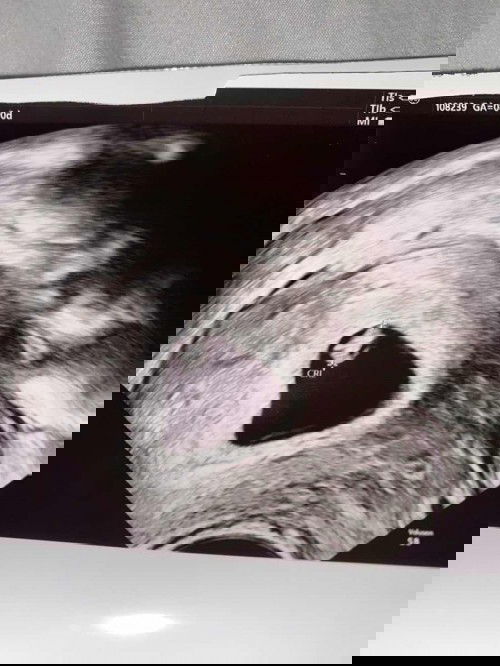

8 MINGGU Kandungan

Alhamdulillah….. Tadi Saya pergi Appoimnt…. Utk scan melalui bawah…..8 Minggu….. Syukur Dugaan Doc Lain Salah…. Dia ckp Kemungkinan Luar Rahim…… Alhamdulillah x…🌹… Sebelum nie saya Kandungan Anggur….. Tadi Doc bagi tgk Degupan Jantung Baby laju Sgt….🥰 Semoga Allah s.w.t Jaga kandungan2 Kita Semua…🤲🏻❤️🌹…